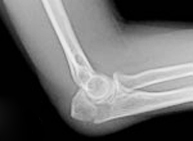

La articulación del codo está formada por las porciones inferior del húmero y superiores de cúbito y radio. Su lesión se produce fundamentalmente tras el impacto de la mano contra el suelo con el codo en extensión, siendo especialmente vulnerables los niños y la tercera edad. Tanto si existe rotura ósea (fractura) como si hay separación entre los huesos de la articulación (luxación) se requiere un diagnóstico eficaz y un rápido tratamiento para evitar la aparición de secuelas.

Fracturas de cabeza de radio

Las fracturas de radio son producidas fundamentalmente de forma indirecta por transmisión de un impacto de la mano hacia el codo. Pueden ser caídas fortuitas o durante la realización de actividad deportiva o laboral. Cuando tienen lugar el codo se inflama y su movimiento es muy doloroso. El tratamiento busca la restitución de la anatomía normal del radio para iniciar el movimiento cuanto antes e impedir la aparición de rigidez.

Fracturas de olécranon

El olécranon es la parte superior del cúbito que articula con el húmero para que podamos realizar la flexión y extensión de nuestro codo. Una fractura de olécranon supone la imposibilidad para la realización de esta función. Ocurren tanto en el paciente de edad avanzada como en el joven y suele ser por caídas con el codo en flexión. Dada su relevancia en el movimiento del brazo su reparación debe ser rápida y precisa para evitar secuelas en la bisagra del codo. A través de procedimientos mínimamente invasivos se puede conseguir la restitución articular minimizando los riesgos de grandes cirugías e iniciar el movimiento en un breve período de tiempo.